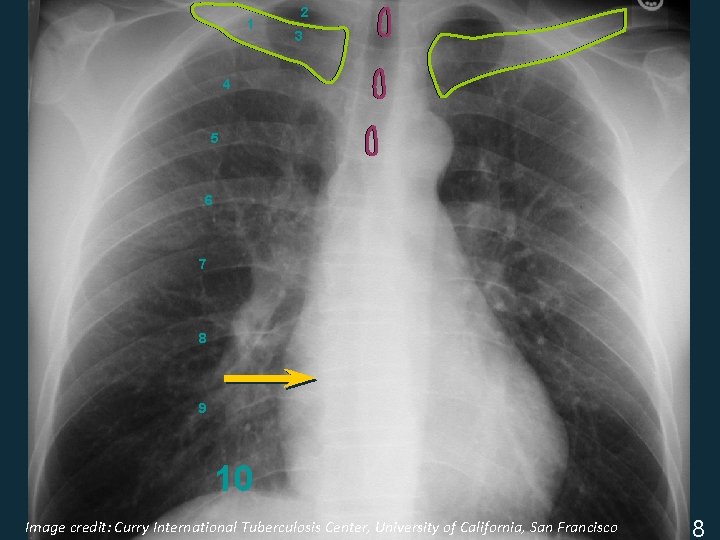

Assess CXR Technical Quality § Inspiratory effort • 9 -10 posterior ribs § Penetration • thoracic intervertebral disc space just visible § Positioning / rotation • medial clavicle heads equidistant from spinous process ISTC TB Training Modules 2009 7

Image credit: Curry International Tuberculosis Center, University of California, San Francisco ISTC TB Training Modules 2009 8

1 2 3 4 5 6 7 8 9 10 Image credit: Curry International Tuberculosis Center, University of California, San Francisco ISTC TB Training Modules 2009 8